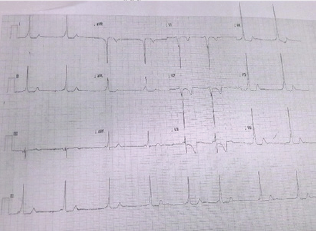

An 11-year-old male of 25kg, known to have WPW syndrome Figure 1, and had a posterior fossa ependymoma resected 2 years earlier was found to have 3 recurrent deposits of the tumor in his cervical spine, frontal lobe and cerebellar area on routine follow- up scanning. Since he was otherwise in considerably good health, a multi-disciplinary decision was made to carry out a precise resection of these secondary tumor deposits, under general anesthesia, facilitated by intra-operative neuro-monitoring. Preoperatively, his GCS was 15/15 and there were no clinical neurological deficits. His WPW syndrome Figure 1 had been stable with no recent symptomatic arrhythmias (Figure 1).

Figure 1: ECG record showing features of WPW syndrome (decreased PR interval, delta waves, wide QRS and associated ST and T wave changes).